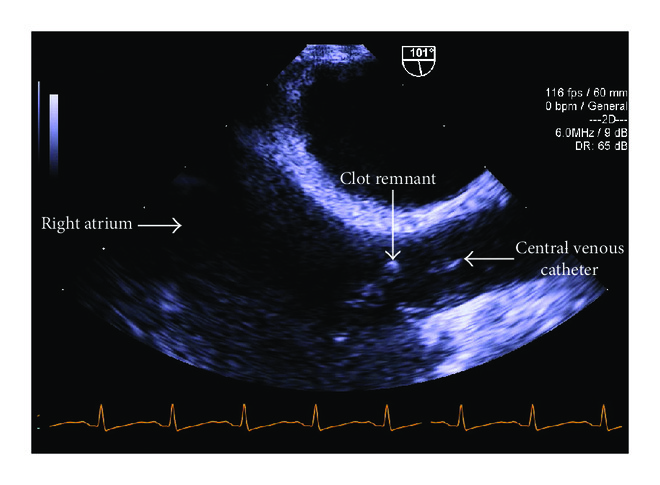

After graft reperfusion, TEE demonstrated a decrease in size of the clot and normal right and left ventricular function (Figure 5).

The patient remained stable throughout the case, requiring transfusion of two units of packed red blood cells (PRBC). The patient was transferred to the surgical intensive care unit postoperatively in stable condition and was successfully extubated on postoperative day (POD) 4. Graft function at that time was normal and there was no evidence of bleeding. The heparin infusion was continued postoperatively for 5 days after which anticoagulation therapy was transitioned to warfarin as soon as the patient was extubated and her surgical drains were removed.

A transthoracic echocardiogram (TTE) performed on POD 1 demonstrated a mobile, shaggy mass suggestive of a right atrial thrombus but was otherwise normal. There was no evidence of right heart strain. A repeat TTE on POD 9 was unable to demonstrate the presence of a clot in the right atrium and was also negative for any right heart strain.